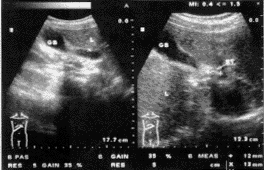

B超检查:肝形态大小正常,回声均匀,肝内血管显示清晰。胆囊26cm×57cm,壁厚4.2mm,毛糙,暗区透声性尚可。胆囊管内径13mm,长32mm(图1左),胆囊管与胆总管汇合处见12mm的强光带反射伴声影(图1右),胆总管内径6.8mm,肝内外胆管未见扩张。提示:1.慢性胆囊炎;2.胆囊管结石可能性大。

图1 胆囊管瘢痕粘连